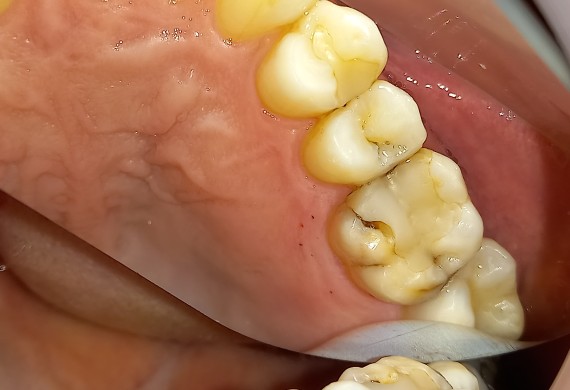

Αρχική κλινική εικόνα του μεγάλου οδοντικού ελλείμματος